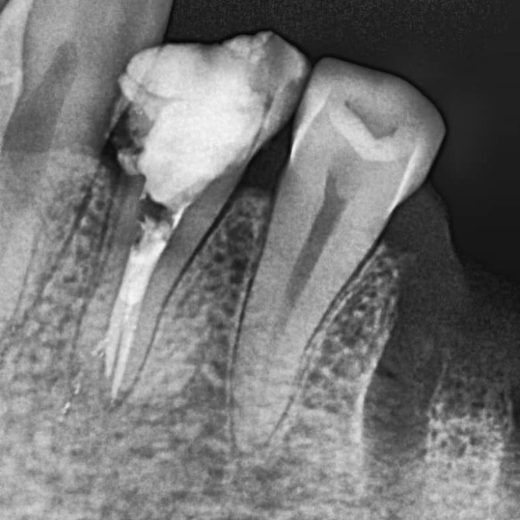

پرمولر سه کانال پایین

3 Canal Lower Premolar